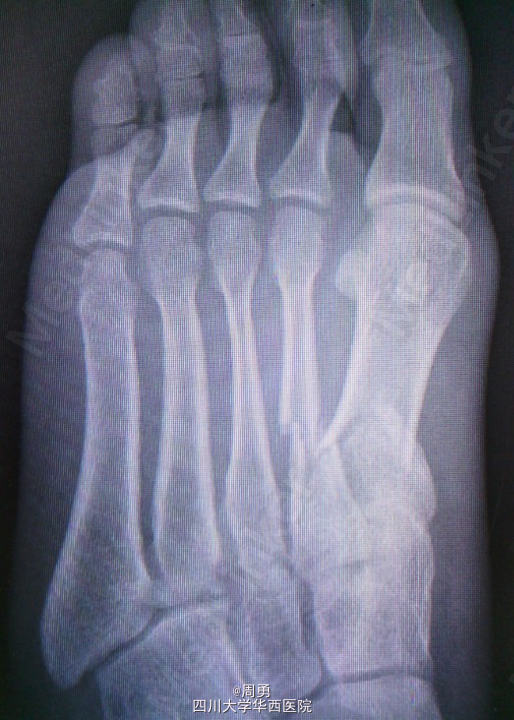

左足第1,2跖骨中近1/3骨折闭合复位克氏针内固定术

此手术为做博士住院总时所做,复位比较满意,价格便宜,效果确实。病例简介:33Y,M,诊断:左足第1,2跖骨中近1/3骨折;处理:行闭合复位克氏针内固定术。